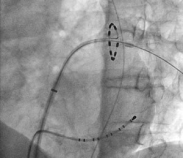

This is a diagnostic test which involves passing wires from the groin to the heart under X-ray control. It can be regarded as an internal ECG, with the additional benefit that we can stimulate the heart with small electrical pulses to examine the electrical system of the heart. It may be that we can trigger previously undocumented palpitations and make an accurate diagnosis. In other cases it may be appropriate to test the heart for any dangerous rhythms.

Ablation can also be carried out for atrial flutter, where a line is drawn in the right atrium to block the flutter circuit. In recent years we have also learnt how to carry out ablation in atrial fibrillation.

In paroxysmal AF, 70-80% success rates are achieved with pulmonary vein isolation. A major discovery in the 1990s was that the triggers for atrial fibrillation are not randomly scattered through the atria as might be expected, but are mainly localised to the pulmonary veins. Various techniques have been developed to achieve this: currently I use the Ablation Frontiers system, which has been shown to achieve success rates of >80% in paroxysmal AF cases.